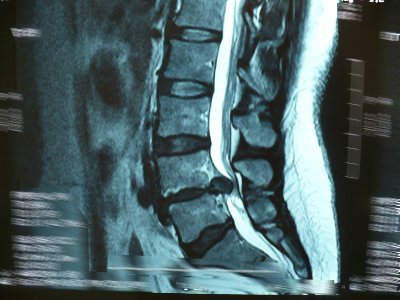

Tumores vertebrales y hernia lumbar